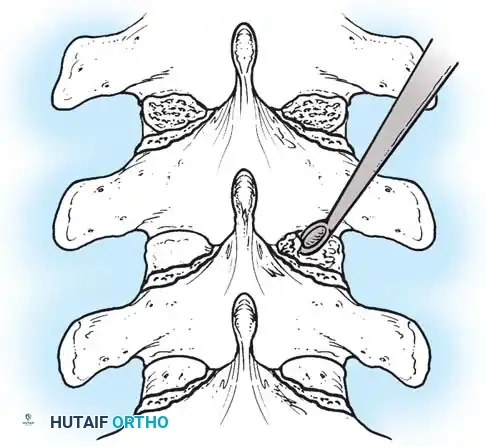

The Moe Technique (Thoracic Spine)

The Moe technique is a highly effective method for achieving intra-articular arthrodesis in the coronally oriented thoracic facet joints.

Fig. 38-26: The Moe technique of thoracic facet fusion, demonstrating the creation of hinged bone flaps.

- Expose the spine fully to the tips of the transverse processes.

- Using a sharp osteotome or Cobb gouge, begin a cut over the cephalad articular process at the base of the lamina.

- Carry this cut along the transverse process almost to its tip. Bend this cortical fragment laterally so it lies between the transverse processes, ideally leaving it hinged on its lateral periosteal attachment to preserve local vascularity.

- Thoroughly denude all articular cartilage from the superior articular process using a sharp curet.

- Make a secondary cut in the superior articular facet, working medially to laterally, producing another hinged fragment.

- Pack the resulting intra-articular defect tightly with cancellous bone graft.